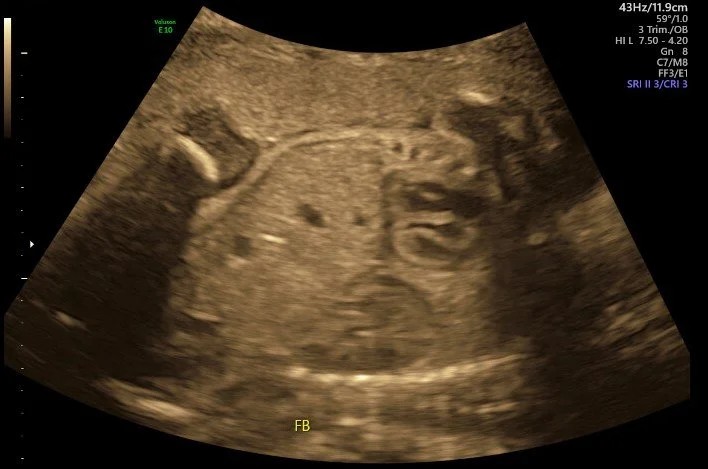

Diaphragmatic Hernia

A suspected absent left kidney sent a sonographer on a hunt to locate it. They did find it, but not where it was supposed to be...